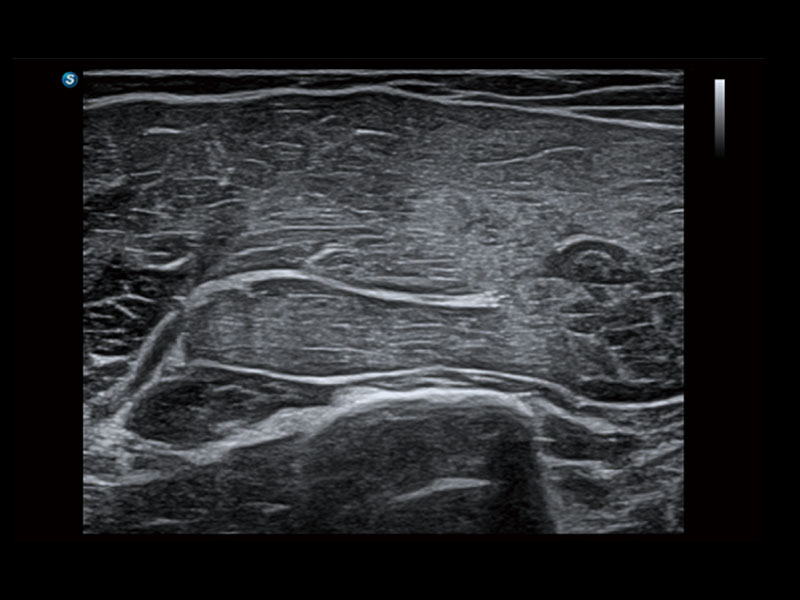

便携式彩色多普勒超声诊断系统

作为开立医疗全新打造的高端床旁笔记本超声,E11不仅具备卓越的图像质量,同时搭载全面高效的自动测量工具,助力医生实现更快速、更精准的床旁诊断。